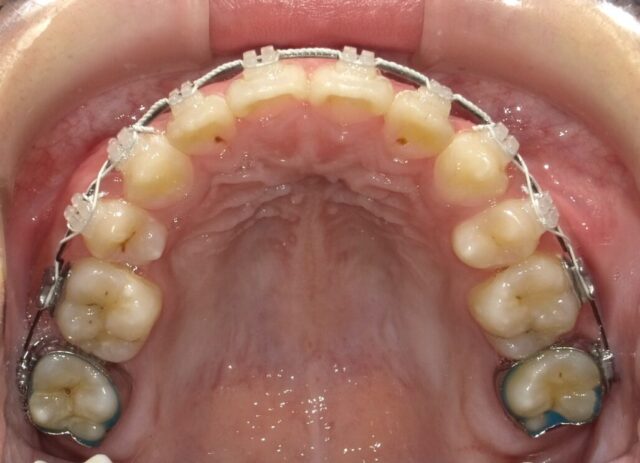

≪上顎咬合面観≫

2023年5月